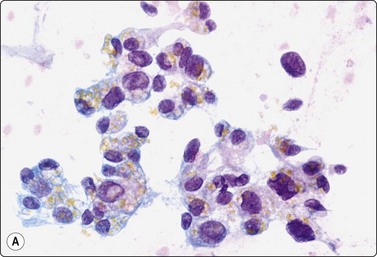

Choriocarcinoma (Fig. 13.39)59,63,66

These tumors most commonly present with symptoms referable to metastases12 and most FNA reports are of extratesticular metastases. Immunostaining for βHCG is helpful to identify syncytiotrophoblastic cells. Large syncytiotrophoblastic cells may also be aspirated from classical seminomas, embryonal carcinomas and mixed TGCT.

image image

Fig. 13.39 Choriocarcinoma

(A) Cluster of cytotrophoblastic and syncytiotrophoblastic cells (MGG, HP); (B) Corresponding tissue section (H&E, IP).